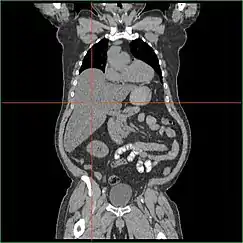

Hepatomegaly via CT scan.

Hepatomegaly with enlarged liver visible in red crosshairs and extending downward.

Impairment in the liver's ability to perform gluconeogenesis leads to clinically apparent hepatomegaly. Without this process, the body is unable to liberate glycogen from the liver and convert it into blood glucose, leading to an accumulation of stored glycogen in the liver. Hepatomegaly from the accumulation of stored glycogen in the liver is considered a form of non-alcoholic fatty liver disease. GSD I patients present with a degree of hepatomegaly throughout life, but severity often relates to the consumption of excess dietary carbohydrate. Reductions in the mass of the liver are possible, since most patients retain residual hepatic function that allows for the liberation of stored glycogen at a limited rate.

Hepatomegaly in GSD type I generally occurs without sympathetic enlargement of the spleen. GSD Ib patients may present with splenomegaly, but this is connected to the use of filgrastim to treat neutropenia in this subtype, not comorbid hepatomegaly. Hepatomegaly will persist to some degree throughout life, often causing the abdomen to protrude, and in severe cases may be palpable at or below the navel. In GSD-related non-alcoholic fatty liver disease, hepatic function is usually spared, with liver enzymes and bilirubin remaining within the normal range. However, liver function may be affected by other hepatic complications in adulthood, including the development of hepatic adenomas.